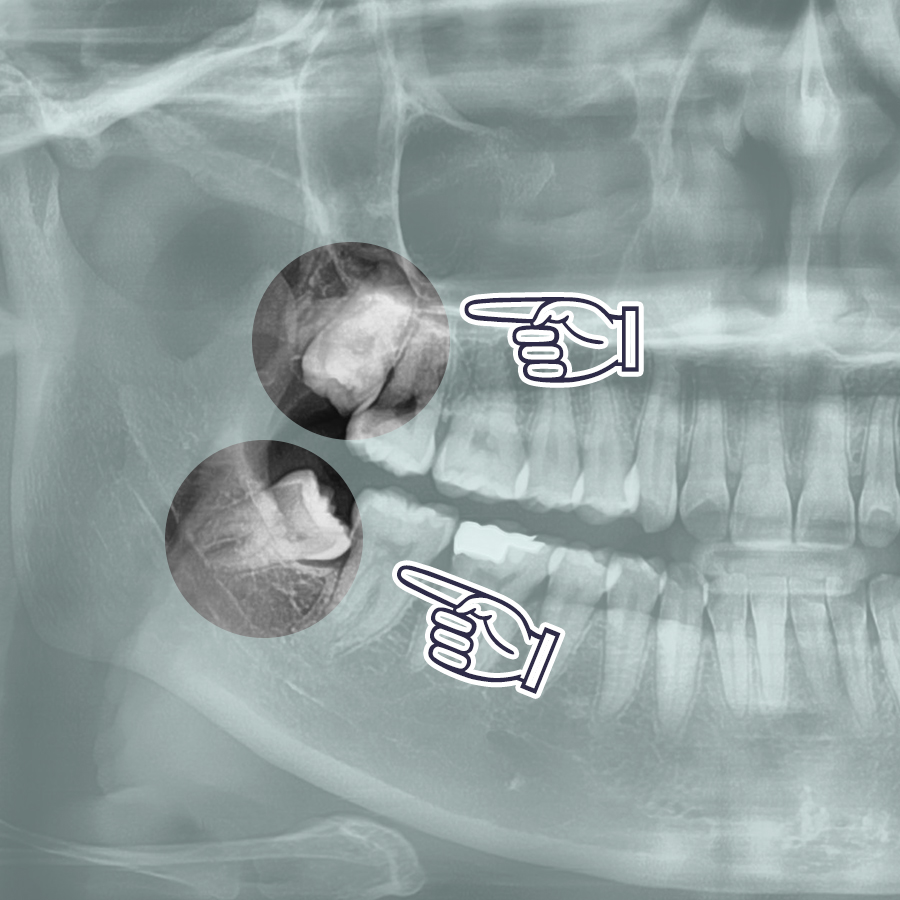

전체적인 치아의 상태를 파악하려 파노라마 엑스레이 사진을 찍어보았죠. 부분 매복 된 아래쪽 이는 턱을 지나는 신경관과 닿아 있는 모습이네요. 그래서 규모가 작은 곳에선 발치를 하기 힘들다 하셨나봐요. 치근단 엑스레이를 추가로 찍었더니 뿌리의 한쪽과 조금 겹쳤어요. 그래도 우리 원장님, 당황하지 않고 CT(보험 비용)를 찍어 3D 결과물을 판독을 하더니 충분히 뽑을 수 있겠다며 자신감을 보여주셨죠! 이 케이스는 뼈를 삭제할 필요는 없고 이도 한번만 분리하면 된다며 생각보다 간단하다고 하셨던 그 말씀이 기억이 나네요.

빠르게 잘 나온 두 치아. 본인 사례가 복잡하고 어려워 걱정했던 것이 무색할 정도로 간단하게 발거가 되었네요. 이 경우는 치관의 1/3이 잇몸 아래로 묻혀 있어 단순매복으로 인정, 뿌리 끝이 신경관가 닿아서 찍은 CT를 합쳐서 토탈 4~5만원 정도로 비용이 나왔죠.